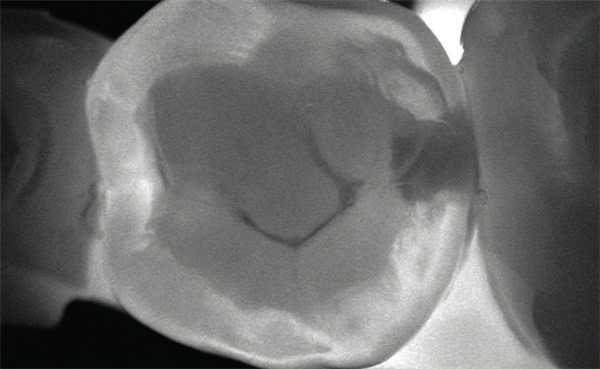

Для диагностики кариеса существует множество методик — от простого осмотра полости рта до применения суперсовременной лазерной технологии DIAGNOcam (рис. 2).

Рис. 2. Сохраненное изображение просвеченного зуба, полученное при обследовании с помощью KaVo DIAGNOcam.